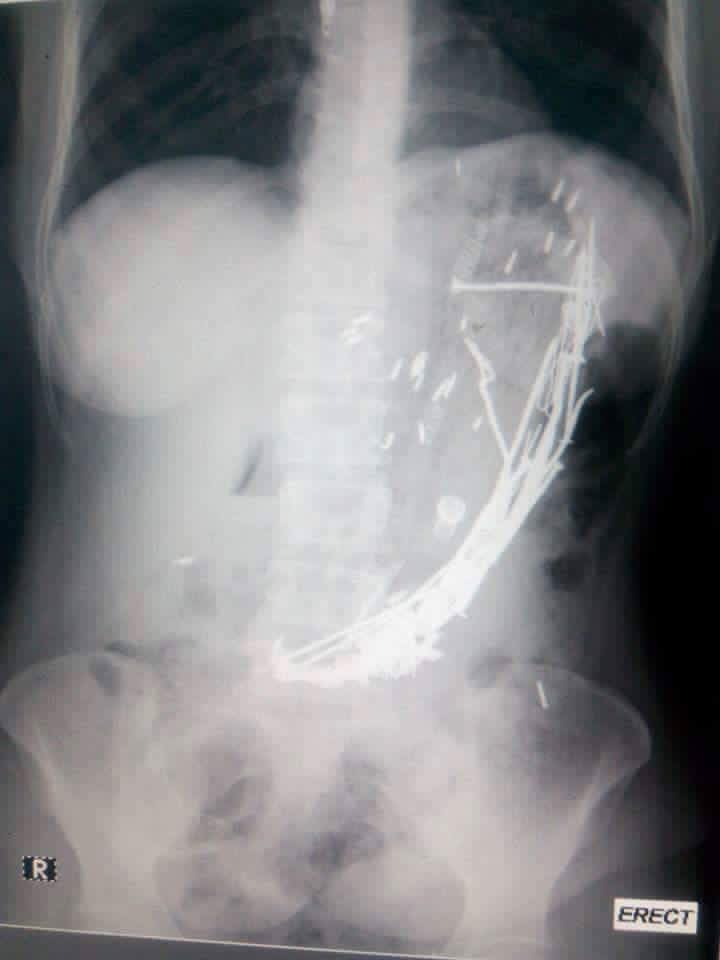

A 43-year-old woman with a medical condition -shocked doctors after series of unwanted items were removed from her body after experiencing abdominal pain and vomiting for 10 days. Nails, pens, spoon, woods, hair, metal chain and tooth brush, were among the items extracted from her stomach after an operation . The graphic photos have been trending on Facebook.